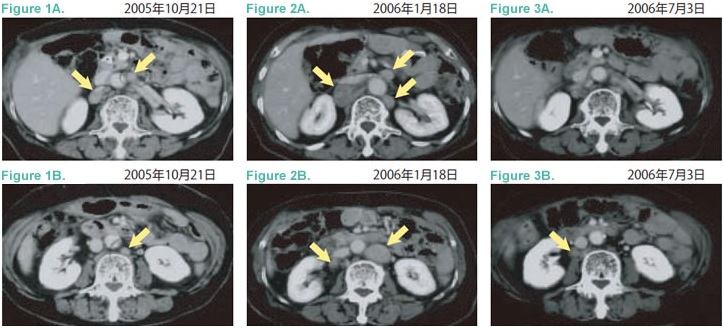

2005年10月肿瘤标志物再上升,腹部CT显示旁大动脉淋巴结复发(Figure1A、B)。化疗副作用腹泻、强烈恶心,体重明显先将,随机中止TS-1,进入维持性支持治疗。2005年11月开始服用中草药。2006年1月18日发现新的淋巴结转移,及原病灶增大(Figure2A、B),左锁骨上淋巴结转移。

2006年3月24日开始询问免疫细胞治疗,PS0,左锁骨上淋巴结肿大可触。4月7日开始体淋巴活化治疗(CD3-LAK),每2周1次。截至6月20日共治疗6次。患者本人定期往福岛县温泉疗养。此间CA19-9指标在下降,左锁骨上淋巴结缩小,触诊已经摸不到。7月3日CT影像显示旁大动脉淋巴结缓解(Figure3A、B)。之后该患者每6周接受一次免疫细胞治疗,直至发稿,患者全身状态良好,食欲佳。